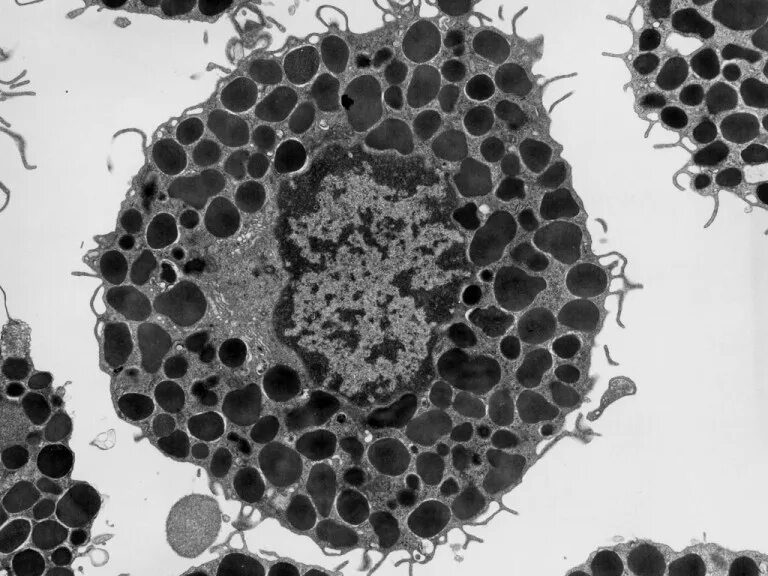

Микроскопия окрашенных